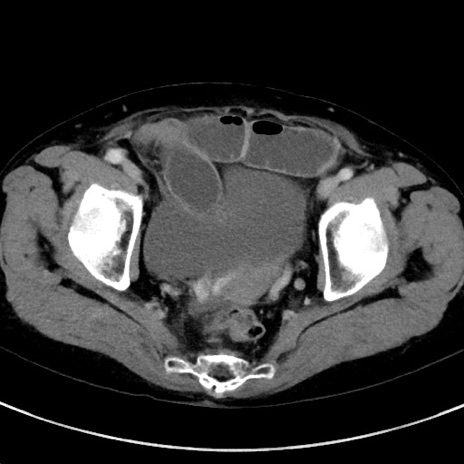

症例23(横断像)

【症例】70歳代女性

【主訴】下腹部痛・嘔吐

【現病歴】2日前より腹痛あり。昨日嘔吐あり。症状改善しないため来院。

【既往歴】胃GISTに対して胃部分切除後。

【身体所見】BT 37.1℃、BP 128/77mmHg、腹部:平坦・軟、下腹部に圧痛あり。

【データ】WBC 10200、CRP 0.31